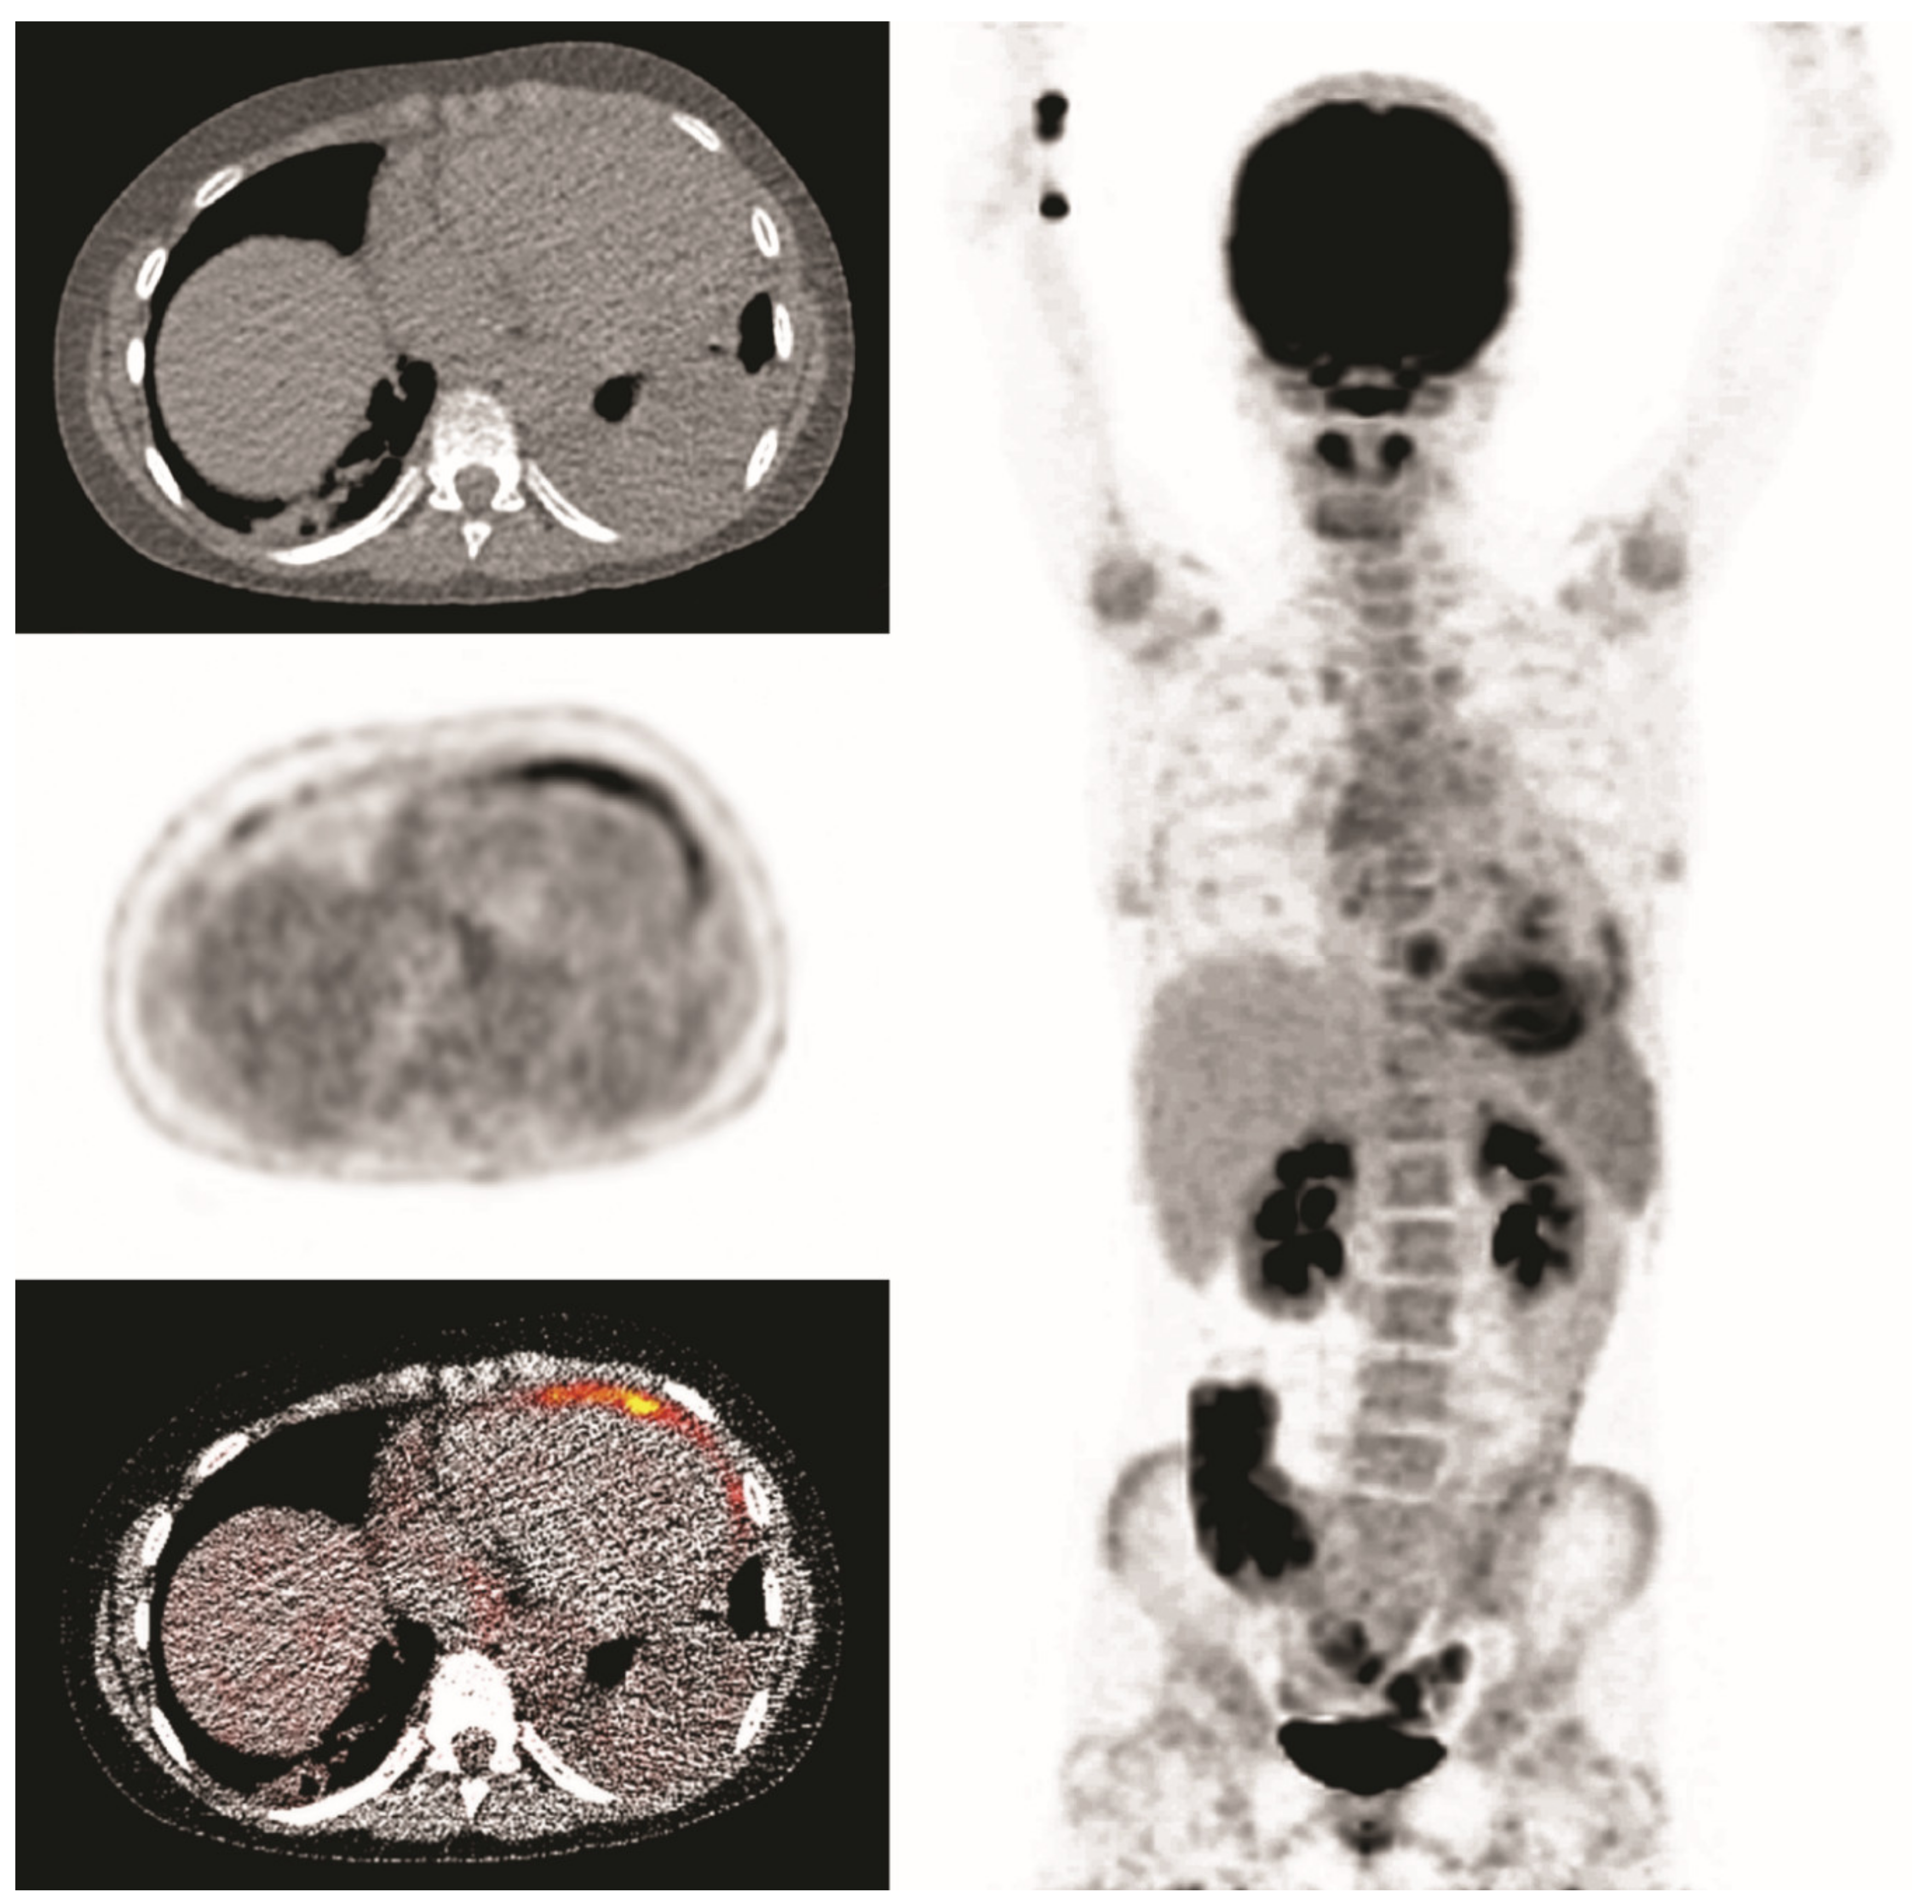

A 14-year-old girl, who previously underwent a mitral valve annuloplasty, was admitted with fever for one week with a maximum CRP of 290 mg/L. Echocardiography did not reveal a conclusive diagnosis. Endocarditis was suspected and FDG-PET/CT was performed after a low-carbohydrate diet. This revealed uptake in the pericardium but no signs of endocarditis (presented images are of first scan). She was treated with antibiotics for 6 weeks, and symptoms receded. However, microbiological testing remained negative. Six weeks after cessation of antibiotic treatment fever returned and a second FDG-PET/CT was performed. It showed similar pericardial uptake, suggestive for persisting pericarditis. She was successfully treated with colchicine, suggesting a non-infectious cause of pericarditis (Figure 5).

Figure 5.

Clinical example 1. Pericardial FDG-uptake is present, most pronounced around the apex and anterior wall.